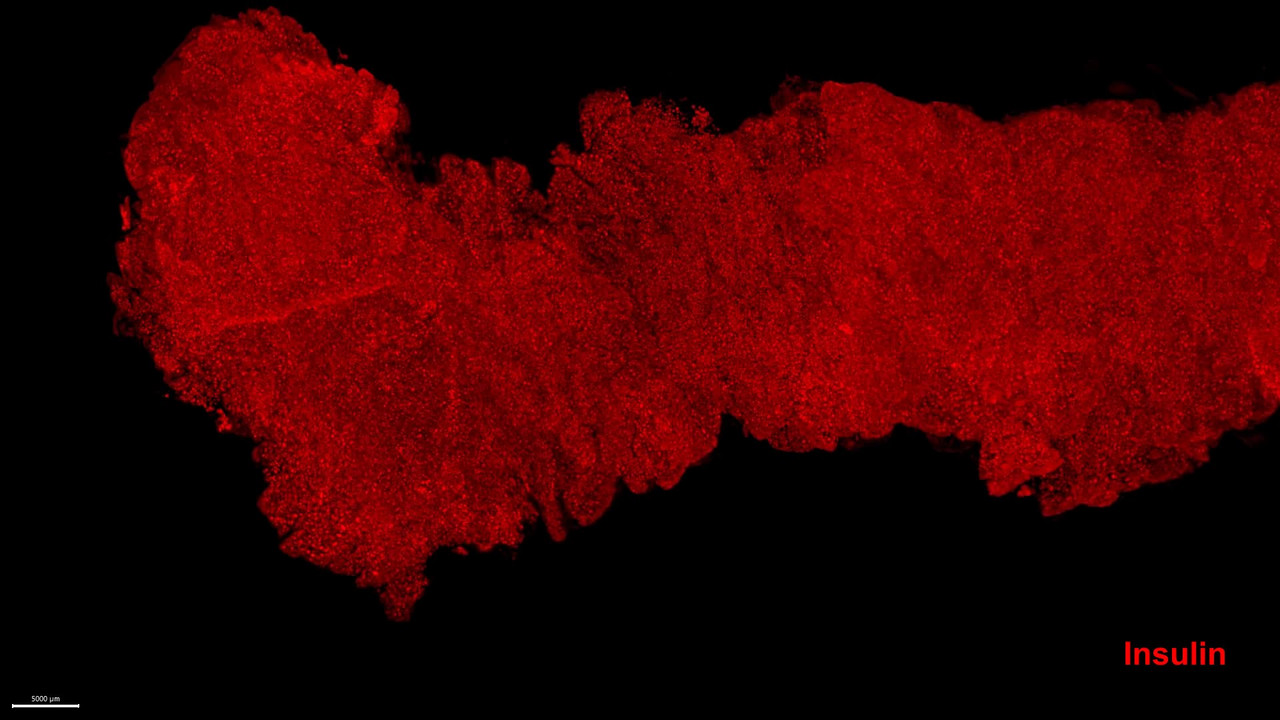

Since the islets of Langerhans make up only a few percent of the pancreas, even though they occur in such large numbers, they have historically been very difficult to study directly within the pancreas. In most cases, researchers have had to study tissue sections that only provide a 2D image of a very small part of the organ. Now, Umeå researchers have used optical 3D techniques in which different cell-types can be marked with fluorescently- coloured antibodies.

"By dividing the entire organ into smaller parts, we enable the antibodies to get where they need to go. Since we know where each piece comes from, we can then, after scanning the different parts individually, ‘reassemble’ the entire pancreas again using computer software. This allows us to perform a plethora of calculations and study which cell-types are present, as well as where they are located in 3D space, as we know the 3D coordinates, their volume, shape and other parameters for each and every stained object in the entire organ.”

Illustrationen visar hur en hel bukspottkörtel (t.v.) från en avliden donator kan färgas in med antikroppar för olika celltyper och avbildas med optisk projektionstomografi (i mitten, Insulinfärgade öar i rött). Den kan sedan studeras i högre upplösning med ljusfältsmikroskopi (t.h.). Det röda är insulin och det gröna glukagon.